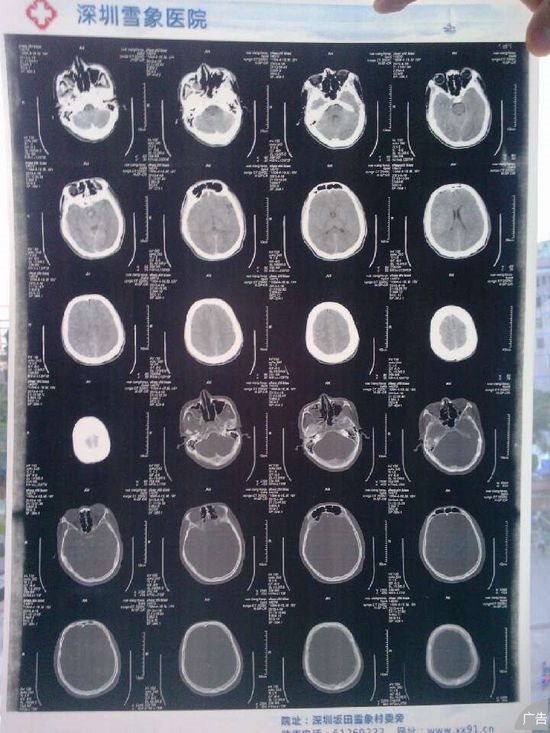

患者赵某,19岁,4月18日9点30分,因“车祸致头部流血不止,昏迷10余分钟”入院抢救。患者在十五分钟前不慎被公交车撞伤头部及全身多处,当即昏迷,呼之不应,躁动,耳鼻出血不止。经120急救车接入院后,李院长批示立即启动“绿色通道”对其进行检查、救治,确定出血灶,诊断为:右颞部硬膜下水肿,硬膜外血肿、颅内血肿、气颅症;蛛网膜下腔出血;脑挫裂伤;右侧颞骨骨折、颅底骨折以及全身多处皮肤软组织擦挫伤。伤者情况危急,没有家属陪护,雪象医院外科团队在科主任赵明义的带领下,立即对伤者进行抢救,给予止血、吸氧、补液、消肿,降颅内压、护脑以及心电监护,科室护理团队积响应,马上建立特护小组对伤者给予特级护理。

4月22日,患者病情得到控制,但是,还偶有情绪烦躁不安、四肢躁动症状。雪象医院外科邀请北京大学深圳医院神经内科吴教授及胡教授会诊,两位医生对伤者进行了详细地体检,认真地查阅了病历,并对整个抢救过程进行分析研讨,与雪象医院外科医生共同制定后期治疗、康复方案。北京大学深圳医院神经内科两位教授对雪象医院在患者抢救过程、前期治疗和护理措施给予度赞扬,特别是“绿色通道”,充分表现了“敬重生命、救死扶伤”的医疗本质。目前,患者生命体征平稳,意识清楚,无进行性出血灶,无手术指征,陈旧性出血也将慢慢地吸收,现行治疗方案正确,再增加营养脑细胞的药,随着治疗时间的延续,情绪烦躁不安、四肢躁动等症状将得到控制。